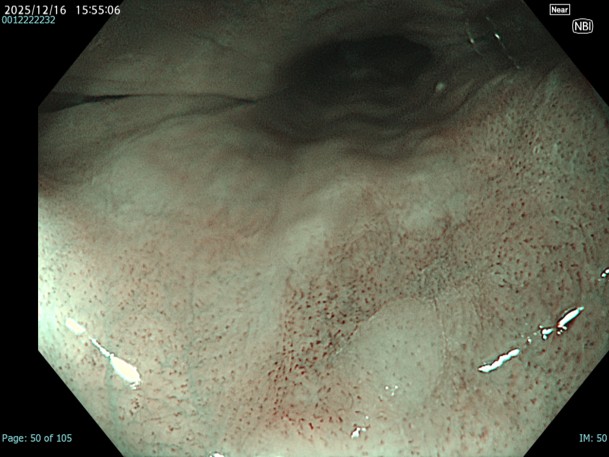

• NBI観察(拡大)

強調設定:A8

図14

NBI-mode、Near-focus拡大。関心領域になるであろう瘢痕部分の拡大観察ではループ構造が崩れたB2血管を認めます。